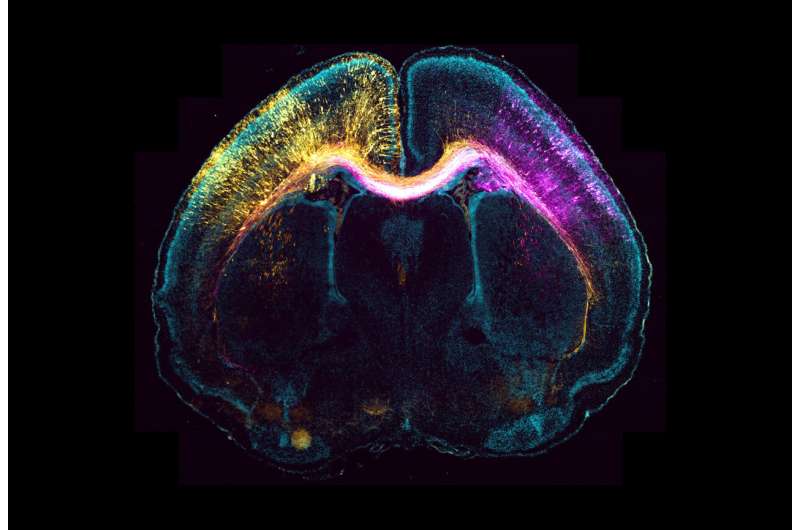

这项研究的重点是神经元的生长和迁移:当神经细胞形成时,它们将大脑连接起来,以实现与其他神经细胞的通信。其中一根轴突变长;这些导线是神经元网络的基础。与此同时,神经细胞迁移到大脑皮层的特定位置。

科学家们在鼠的大脑中发现,轴突的形成独立于中心体的活动。然而,神经元迁移受到显著影响。Dupraz总结说:“轴突的生长显然是由一种不同的机制造成的,即所谓的微管的中心体形成。这将成为我们未来研究的主题。”